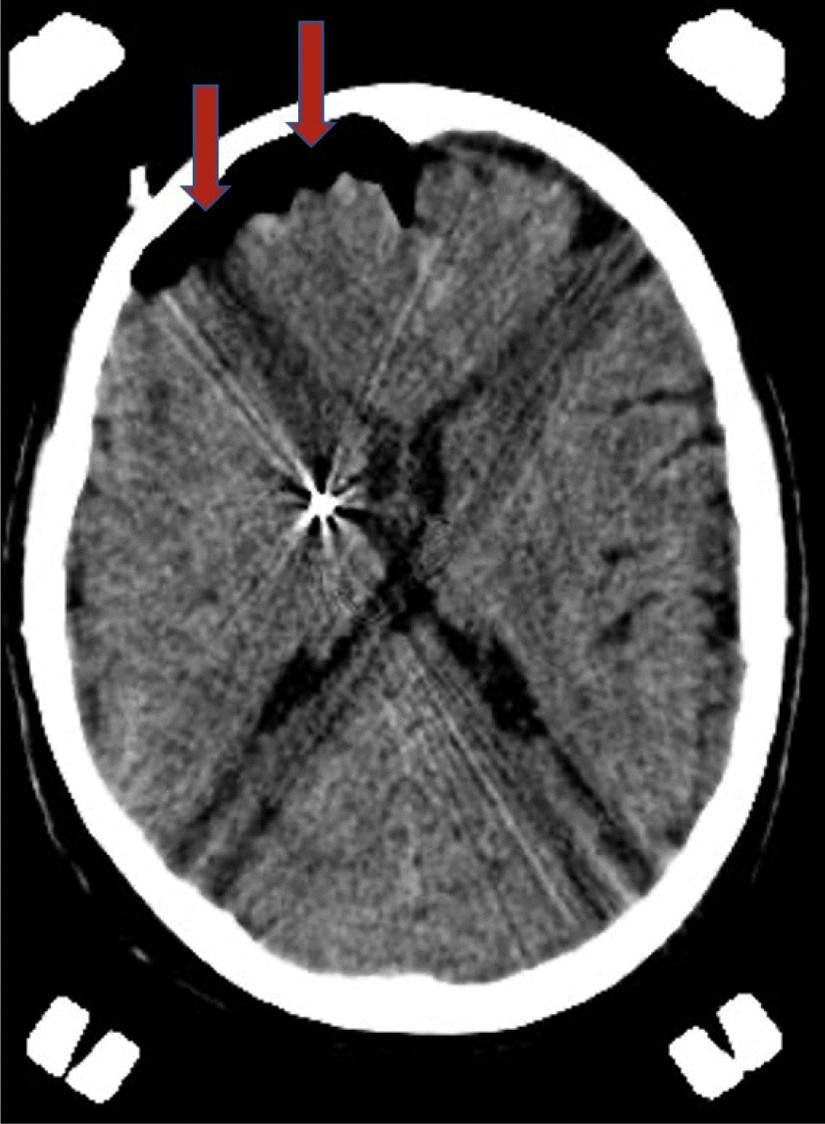

Figure 5

From: MER and increased operative time are not risk factors for the formation of pneumocephalus during DBS

CT scan performed after a unilateral DBS procedure showing the entry of intracranial air (indicated by the red arrows) ipsilateral to the implanted electrode. CT computerized tomography, DBS deep brain stimulation.